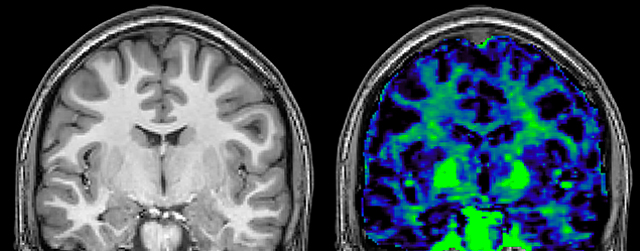

T1 - Weighted, Myelin Water Fraction Superimposed

MWI Spinal cord coverage

Spinal cord coverage

MWI Smaller, more isotropic voxels

Smaller, more isotropic voxels

MWI Excellent detail in quantitative maps

Excellent detail in quantitative maps

Images courtesy of Adam Dvorak, Department of Physics and Astronomy, University of British Columbia

20%

Myelin water fraction

0%

Myelin water imaging (MWI) is a breakthrough technique that was pioneered at UBC for measuring myelin content in the brain, in vivo. “Because the T2 time of water in myelin is much shorter than the T2 of water in the intraand extracellular spaces, we can separate out the myelin water signal.”

The techniques for measuring myelin have changed a lot over the years. “Since we are using the Elition, our myelin water images are much better. We're now acquiring 1 x 2 x 5 mm voxels and displaying at 1 x 1 x 2.5 mm. For a whole brain we can now measure the fraction of water in the myelin component in only about five or six minutes,” Dr. MacKay says.

Dr. Rauscher says, “For MWI we perform 3D T2 with 32 or more echoes. This used to take a long time, but with Compressed SENSE we can decrease this to ten minutes for the whole head. Because of the large field of view (FOV) on the readout direction, we even get information from the brainstem, which we previously missed when we were using the GRASE approach. Having the whole head scan is nice because it has spatial resolution, orientation and FOV that are comparable to the standard 3D clinical MS scans, including the FLAIR and 3D T2, and a 3D T1 for brain volume.”